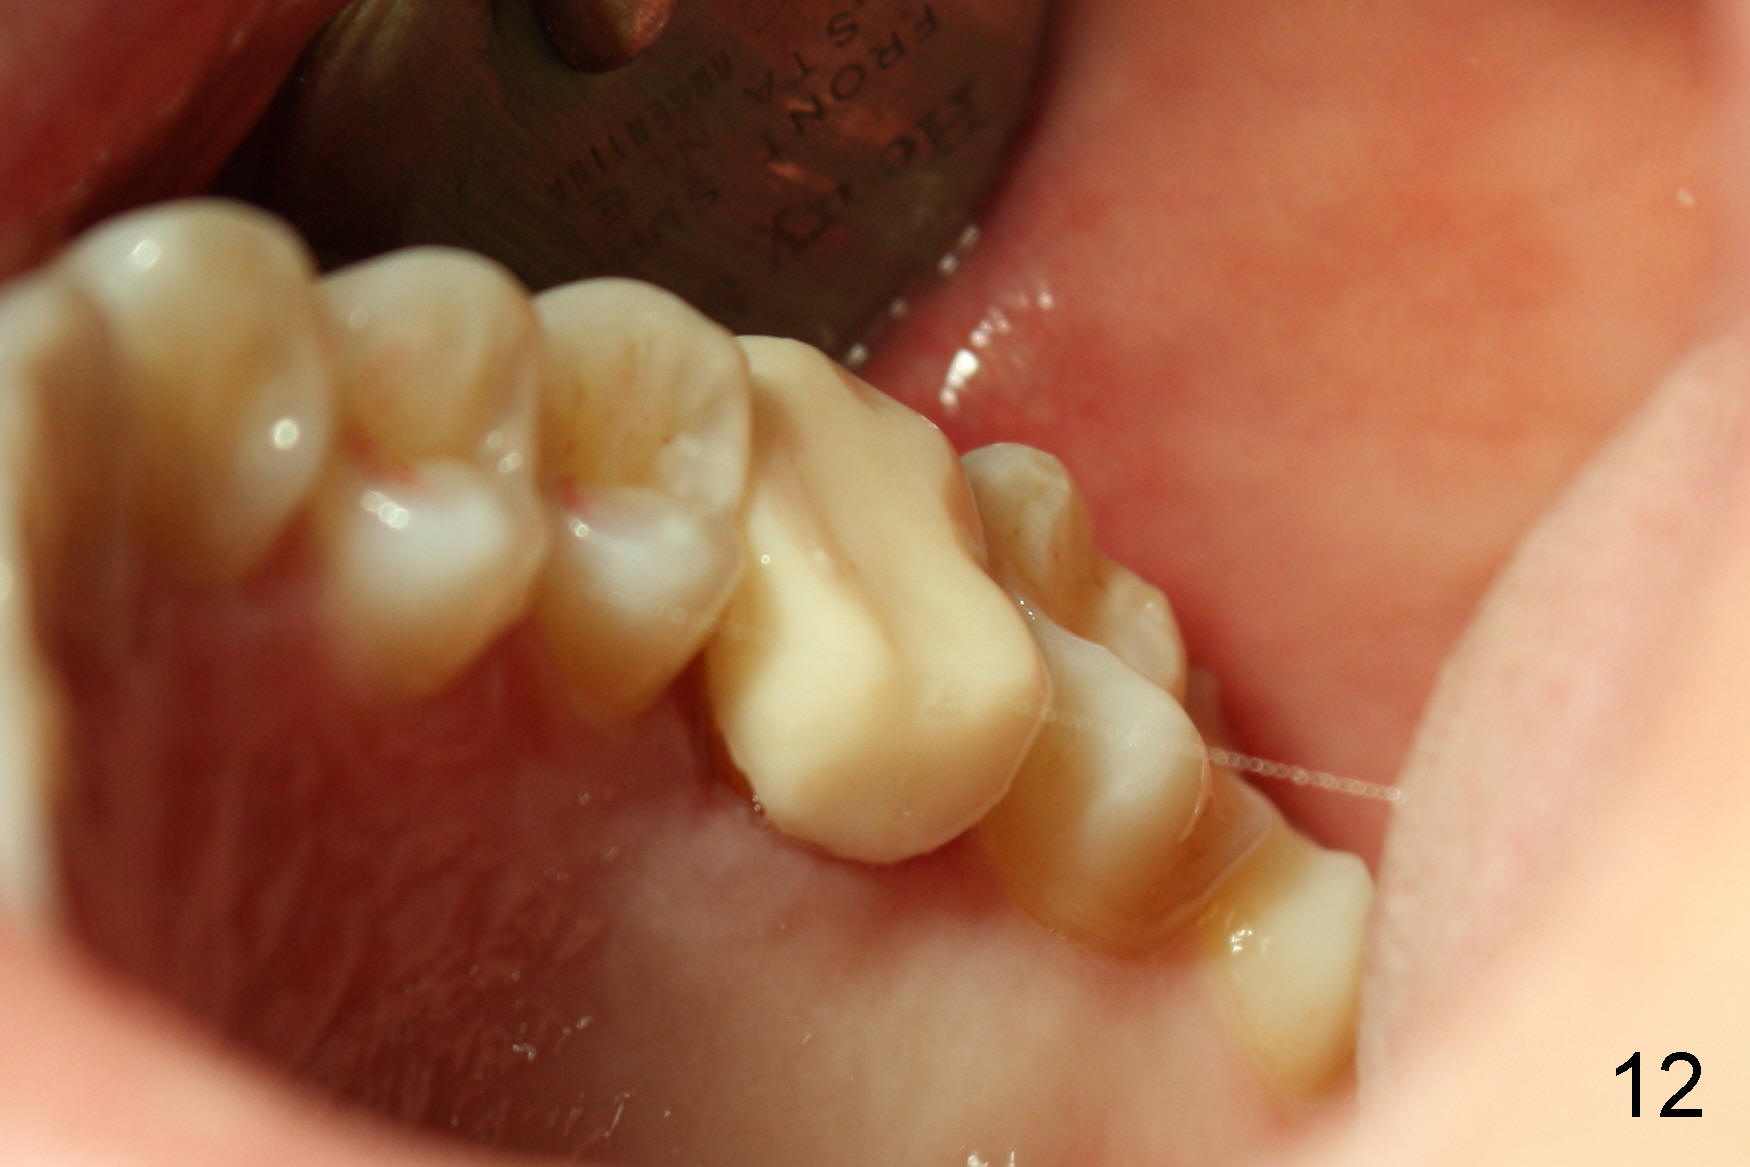

一旦下颌牙冠决定后,适当调整上牙牙冠制备,制做临时牙冠,咬合仿佛改善不少(图十一,与图七比较),上颌临时牙冠低多了(图十二,与图六相比)。在气急败坏下,突然领悟到一个真理:缺失一个磨牙,邻近咬合变化是巨大而且复杂的,例如下颌第二磨牙,不仅往近中倾斜移位,而且往舌侧倾倒(图一,二),发生三维变化,图十二还显示上颌前臼齿也不整齐,大概第二磨牙也有不同程度位置变化。